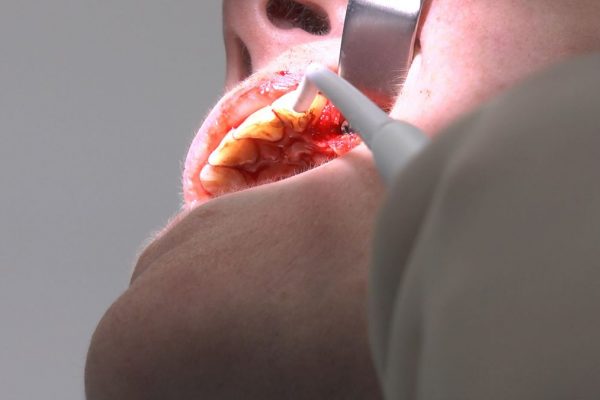

W ostatni weekend czerwca 2018 roku kursanci II Sezonu Preludium Implantologii odbyli piątą, finałową sesję, która w całości podporządkowana była praktyce. W ciągu dwóch dni zabiegowych Lekarze uczestniczący w szkoleniu przeprowadzili szereg zabiegów pod kierunkiem dr n.med. Violetty Szycik. Wszczepili 17 implantów oraz przeprowadzili ekstrakcje i zabiegi regeneracyjne kości. Zabiegi były wykonywane także w sedacji dożylnej z udziałem specjalisty anestezjologii i intensywnej terapii dr Jolanty Grzybowskiej. Preludium implantologii to nowy program edukacyjny dla adeptów implantologii stomatologicznej, którego celem jest wprowadzenie do implantologii poprzez pozyskanie wiedzy w szerokim zakresie i uwzględnieniem szczegółów mających decydujące znaczenie dla powodzenia leczenia implantologicznego. Ale tak jak wszystkie szkolenia w Instytucie Vivadental, w tym wiodące Practiculum Implantologii, zorientowane jest na praktyce i samodzielnym wykonywaniu zabiegów pod kierunkiem Mentora. To najlepsza edukacja w medycynie zabiegowej, a zarazem najlepszy start do implantologii.